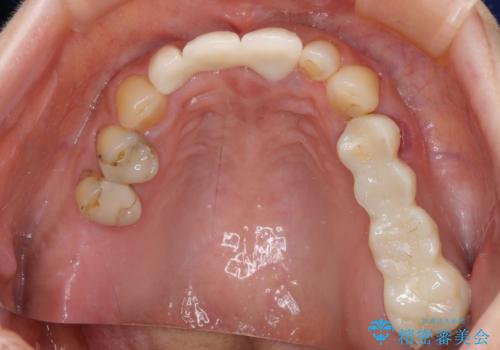

折れてしまった前歯 オールセラミックブリッジで自然な口元に

折れてしまった歯は抜歯せざるを得ないため、抜歯と同時に仮歯を装着し、その後オールセラミックブリッジにて補綴することとしました。

折れた前歯を抜歯すると、歯肉が痩せてしまい、ブリッジの形態の審美性が失われることがあります。仮歯を調整することで審美回復が必要であるか判断しますが、今回は歯肉移植を行うことなく補綴治療を行いました。